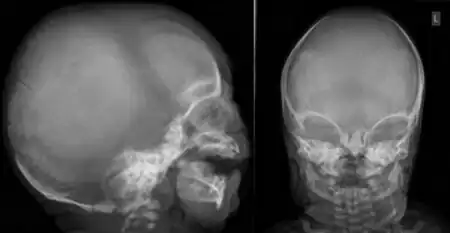

The conditions are characterised by skeletal abnormalities, cleft palate (a hole in the roof of the mouth), and hearing loss.[1] These symptoms are common to craniofacial syndromes as a whole.[3] Hand defects are particularly associated.[2] Of the conditions, OPD1 has the milder phenotype, with normal intelligence and modestly reduced stature.[2] In OPD2, the characteristic facial features are more severe and intellectual disability frequent; most OPD2 cases in males are stillborn or die during infancy.[1][2] As an X-linked recessive disorder, both forms are generally more severe in males, who have one X chromosome, than females, who have two.[4] Reports from patients of their experiences demonstrate a broad spectrum of symptom severity, including within families,[5] which has also been reported in the medical literature.[6]